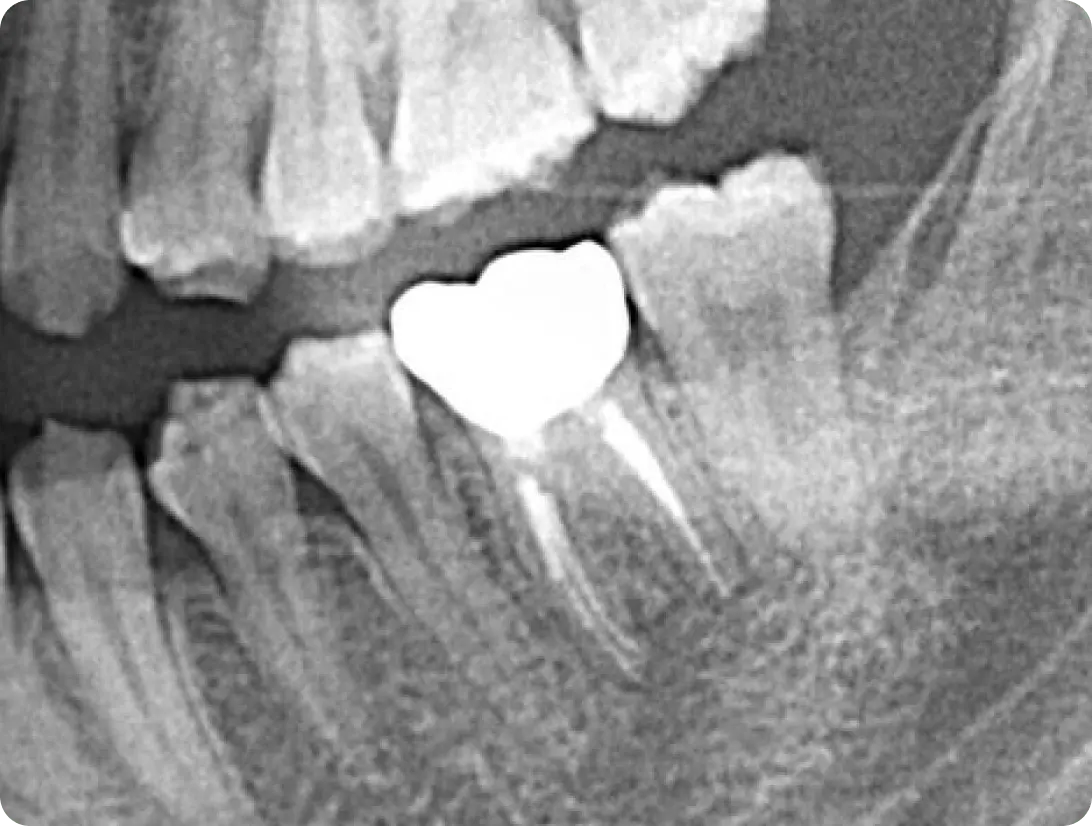

診査・診断

お口の中の診査、レントゲン撮影を行います。

この検査に基づいて原因を洗い出し、最適な治療方法の検討いたします。